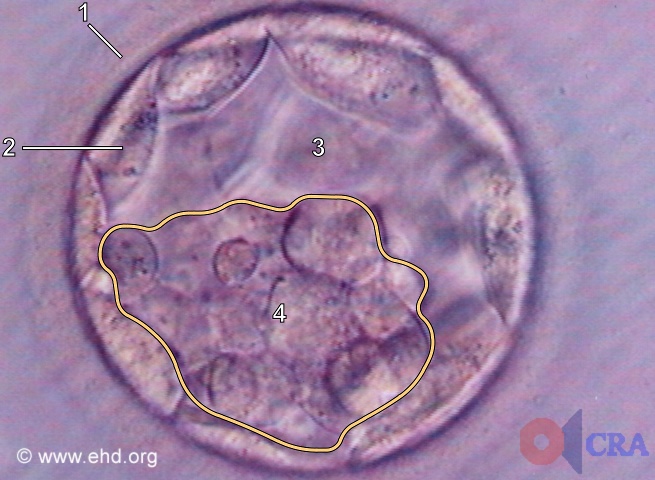

Визуально бластоциста на 5 день под микроскопом выглядит как пузырёк с жидкостью и группой клеток, которые постепенно организуются в будущие ткани.

Фотографии бластоцисты на 5 день помогают врачам и исследователям оценить качество эмбриона перед его возможной имплантацией.

Для получения точных результатов при изучении бластоцисты важно использовать высококачественные микроскопы, которые позволяют увидеть детали клеточной структуры.

Микроскопические изображения бластоцисты помогают медицинским специалистам исключить возможные аномалии и выбрать самые здоровые эмбрионы для трансплантации.

Для точной диагностики и планирования дальнейших шагов в процессе ЭКО врачи внимательно анализируют бластоцисту, обращая внимание на её форму и состав клеток.

Если вы хотите лучше понять процесс развития эмбриона, фотографии бластоцисты на 5 день под микроскопом будут полезным визуальным материалом для изучения этой сложной темы.